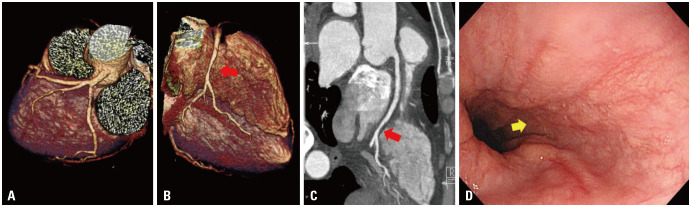

男,55岁,血友病A,过量注射凝血因子后胸痛数日就诊门诊。他烟瘾很大,而且长期酗酒。心电图未见明显变化。冠状动脉ct显示右冠状动脉远段中度狭窄伴软斑块。通过抗心绞痛和反流药物治疗,他的疼痛得到了改善。20天后,他跑到急诊室,抱怨胸部挤压痛。心电图显示下区ST段轻度抬高。经右桡动脉侵入性冠状动脉造影显示同一病变处严重血栓闭塞。在常规血友病治疗下,放置裸金属支架,并维持阿司匹林和氯吡格雷双重抗血小板治疗6个月。患者仅接受单次氯吡格雷治疗5年未发生任何冠状动脉事件,直至因胰腺癌去世。我们的病例表明,对于合并急性冠脉综合征的血友病患者,在维持常规凝血因子剂量的同时,侵入性冠状动脉介入治疗和术后管理可以在常规护理标准下安全进行。

A 55-year-old male with hemophilia A came to the outpatient clinic with chest pain for several days after overdose injection of coagulation factor. He was a heavy smoker and a chronic alcoholic. An electrocardiogram (ECG) showed no specific change. A coronary computed tomography showed moderate stenosis with soft plaque at the distal segment of right coronary artery. His pain was improved with antianginal and reflux medications. Twenty days later, he ran to the emergency room complaining of squeezing chest pain. ECG showed mild ST segment elevation in inferior territories. Invasive coronary angiography via right radial artery revealed severe thrombotic occlusion at the same lesion. A bare metal stent was deployed and dual antiplatelet therapy including aspirin and clopidogrel had been maintained for 6 months under the conventional hemophilia management. The patient did not develop any coronary events just with single clopidogrel therapy for 5 years until he passed away from pancreatic cancer. Our case implicates that the invasive coronary intervention and post-procedural management could be safely performed with conventional standards of care while maintaining the usual dose of coagulation factors in a hemophilia patient with acute coronary syndrome.